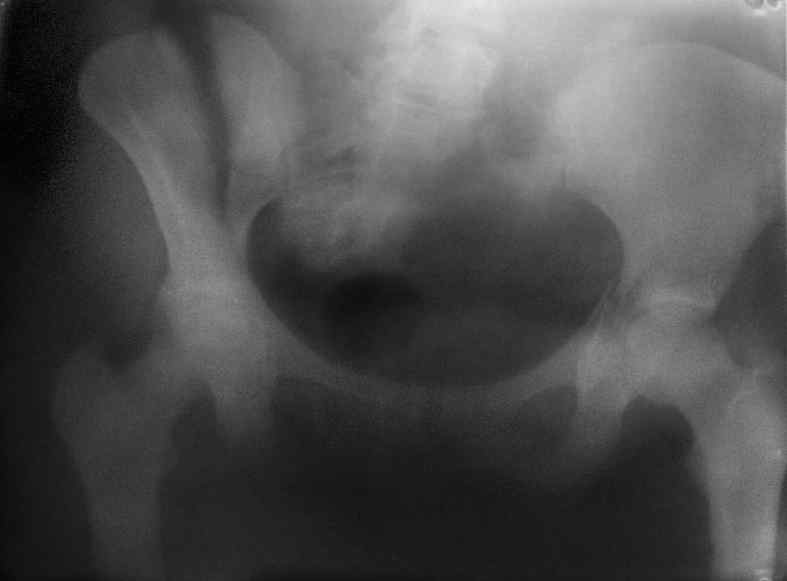

Здравствуйте, коллеги. Какие будут мнения по поводу лечения представляемой больной?

Молодая девушка 19 лет, травма 1 год назад, тогда же прооперирована.

В настоящее время имеются ноющие боли в области крестца слева, нарушение походки, ощущение неуверенности, слабости в левой нижней конечности, неврологически -непостоянные парестезии в левой нижней конечности. Ходит с дополнительной опорой, страдает от ожирения.

Какова по вашему будет оптимальная тактика в отношении несращения крестца? Замена винтов на более длинные с коррекцией их положения+ туннелизация зоны нестращения, открытое вмешательство с костной аутопластикой или еще какие варианты?

В приложении снимки при поступлении и послеоперационные год назад.

Могу сказать одно: миграция винтов и нестабильность синтеза левого подвздошно-крестцовогоо сочленения очевидна.